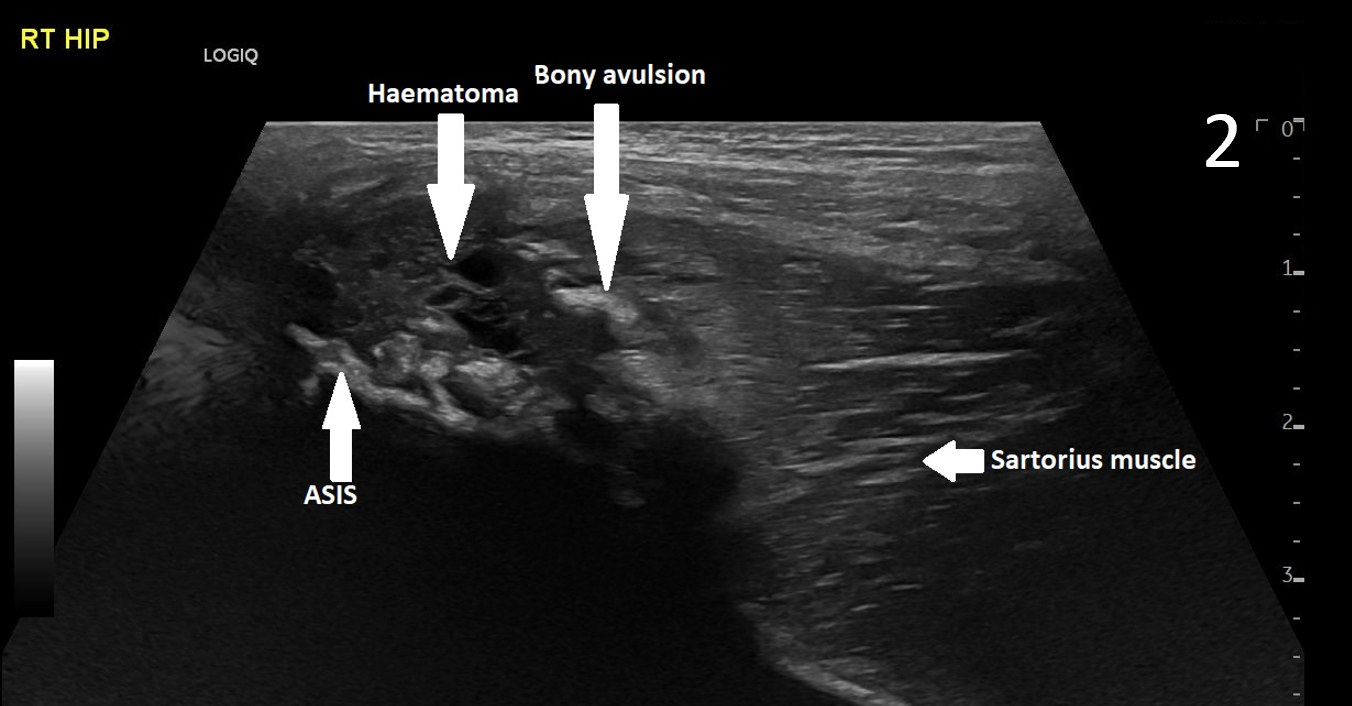

A 17-year-old male presented with severe pain in his right groin. He felt a ‘pop’ in his right groin whilst sprinting and was struggling to weight-bear. A radiograph excluded any bony abnormality (Figure 1) and an ultrasound scan showed no evidence of inguinal or femoral hernia.

The patient was focally tender in the right iliac fossa at the level of the anterior superior iliac spine (ASIS). At this site, there was muscle fibre disruption and a haematoma at the insertion of the sartorius tendon with minimal retraction (Figure 2). There was cortical irregularity at the ASIS and a bony fragment within the retracted tendon and also neovascularisation here on power Doppler (Figure 3). On comparison to the contralateral side, there was altered architecture of the sartorius muscle with a clear defect while the left side looked normal (Image 4). Ultrasound appearances in keeping with a sartorius tendon avulsion. This was treated conservatively with rest, analgesia and a return to normal activities after two months. Surgical interventions are uncommon and are reserved for when the fracture fragment has migrated more than 3cm.

This injury is associated with young athletes plus young rugby and football players.